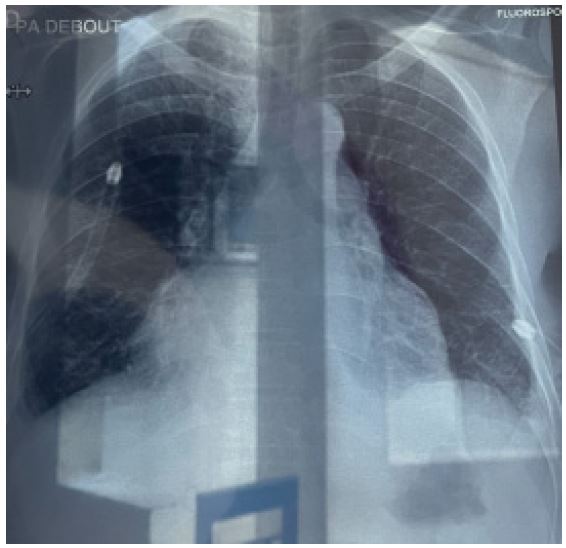

Presenting a 50-year-old immunosuppressed patient who was referred to our hospital for management of massive pre-tamponade pericardial effusion in respiratory distress. Patient was received in the emergency department and an emergency cardiac echography was done which confirmed the referral diagnosis of massive pre-tamponade pericardial effusion with massive bilateral pleural effusions. Patient was immediately prepared and taken for subxiphoid surgical drainage.

Patient was placed under general anesthesia, intubated and placed in the supine position on the surgical bed. Routing disinfection and surgical prepping was done. A subxiphoid median incision starting from xiphoid process to about 7 cm inferiorly was made. Subcutaneous and muscle fascia dissected and the xiphoid process amputated for better exposure of the pericardium. The bulging pericardium seen with a pericardiotomy made gently on the pericardium. Approximately 2 Liters of serohematic pericardial fluid was drained and a pericardial drain was placed in the pericardial space and connected to a self-expanding vacuum drain which was intended to drain the rest of the pericardial fluid. A biopsy of the pericardium was collected alongside 10cc of pericardial fluid and send for histo-cytology studies to determine the etiology of the effusion. Two thoracic drains were also placed and suture wounds closed up according to standard fashion and patient was taken to the surgical ward afterwards. Post operatively, cardiologist and infectious disease consults were requested for the patient. Post operative follow up was done. Histo-cytology results confirming TB as the etiology of the effusion. Patient was placed on anti TB medimedications by the infectious disease doctor and patient improved clinically and symptomatically with drained not producing anymore. Patient was later discharged 10 days post operatively and reviewed 2 weeks after with follow up cardiac echo and chest Xray not showing any pericardial effusion and pleural effusion respectively.